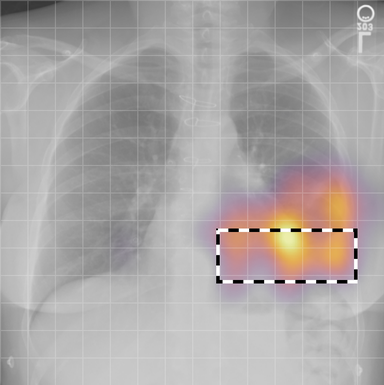

| (1) |

for , where denotes 2D sinusoidal positional encodings [12] and is its temporal counterpart, which is learnt (Fig. 2) [4]. The layer-normalised () [6] output of the final transformer encoder block is an ‘aggregated’ representation of patch-level progression information anchored on the current image. Figure 3 shows attention roll-out [1] applied to after pre-training, showing how the prior image contributes to the fused representation. Figure A.5 further highlights the robustness to variations in pose underlining that registration is not necessary for this encoder.

In Figure A.3, we show examples of self-attention rollout [1] maps for pleural effusion and consolidation, including radiologist-annotated bounding boxes surrounding the corresponding pathology in each prior and current image.

To model the attention flow through the transformer encoder block, we first average each attention weight matrix across all heads, subsequently we multiply the matrices between every two layers. For every block we add the identity matrix in order to model the residual connections. Last, we only keep the top 10 of attention weights per block to reduce noise in the final rollout map. In contrast to [21], we do not visualize the rollout map with respect to a [CLS] token. Instead, we choose a reference image patch from the center of the radiologist-annotated bounding boxes, marked with in Figure A.3.

We find that the rollout maps in Figure A.3 are in good agreement with radiologist-annotated bounding boxes, i.e., the reference patch attends to other patches within the bounding boxes in the prior and current image. In addition, we find that BioViL-T is robust to pose variations, e.g., in Figure A.3 (a) we show that despite the vertical shift between prior and current image, the reference patch attends to the correct image patches in the prior image.